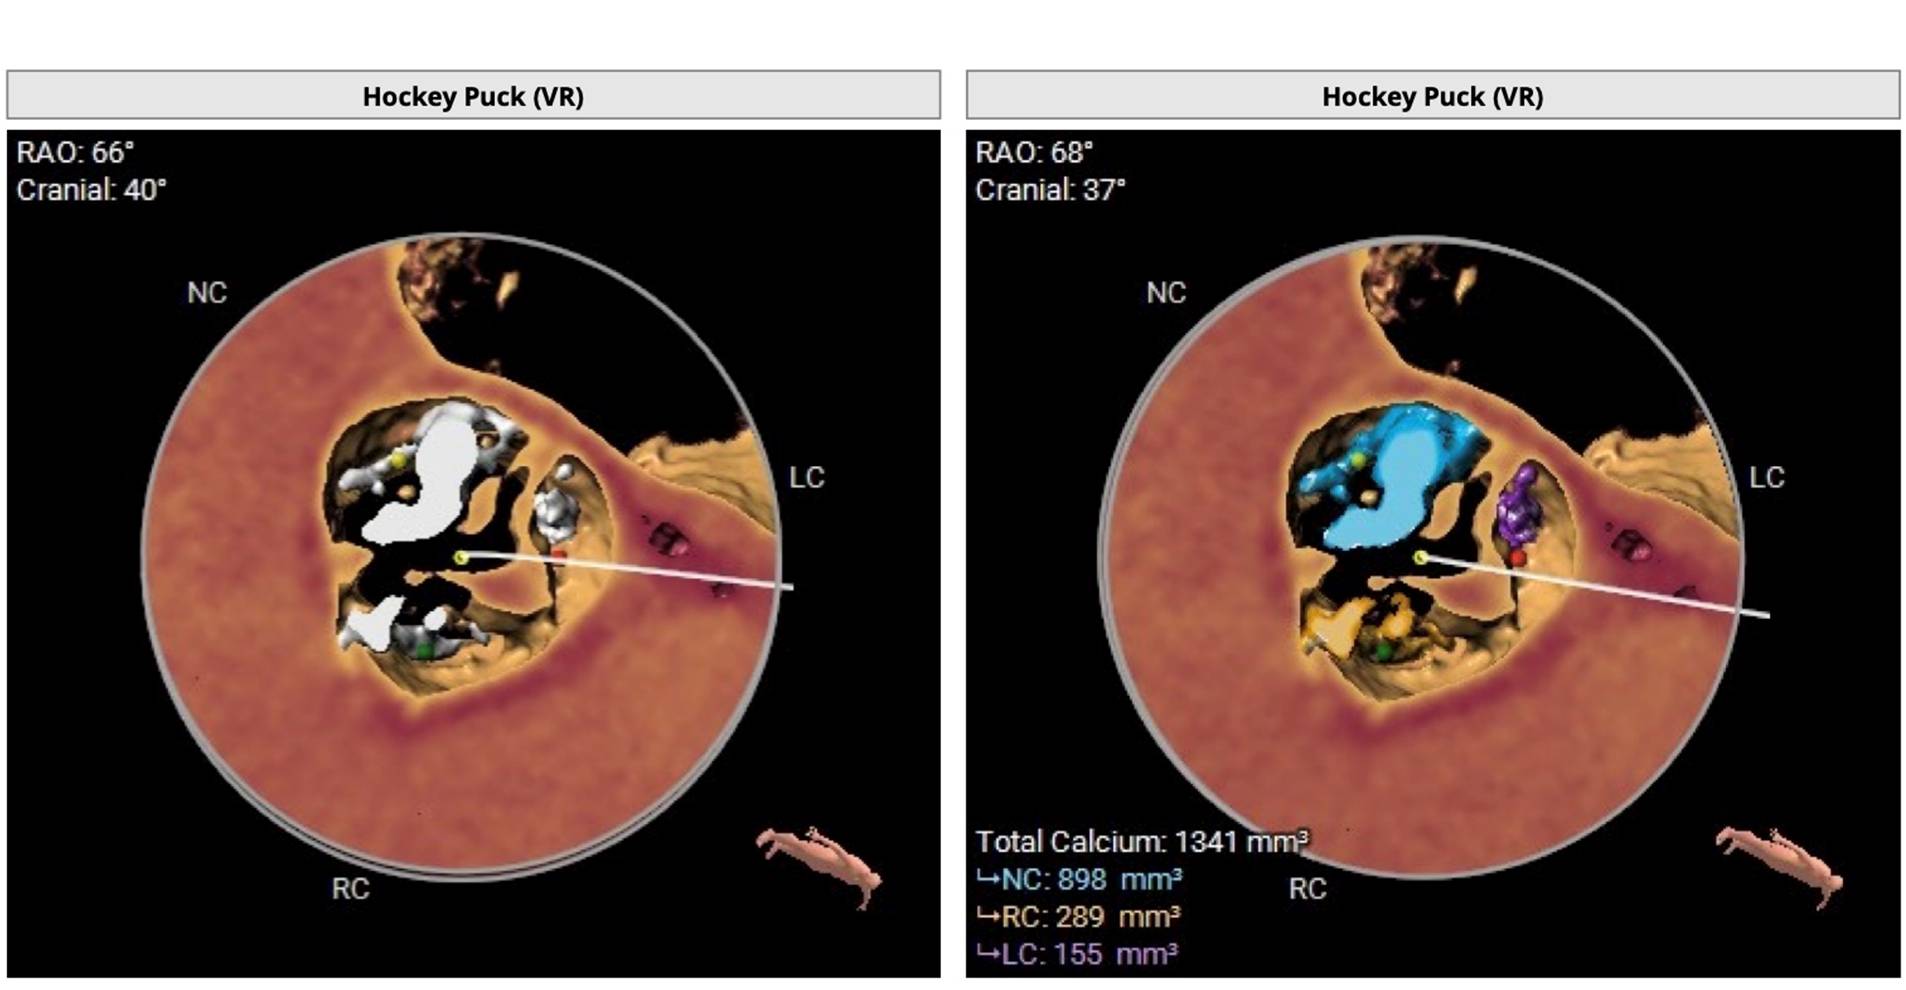

A super-rigid guidewire was inserted into the left ventricular cavity, and a valvulotomy was performed using a 23x40mm balloon catheter. After this, a successful implantation of a Portico 29mm aortic prosthesis was performed. During suturing of the access site, the patient developed persistent hypotension and bradycardia. A decision was made to perform catheterization of the left coronary artery trunk. During the angiogram, compression of the left coronary artery trunk by a hematoma in the projection of the fibrous ring was revealed. A decision was made to perform stenting of the left coronary artery trunk. The stent was successfully implanted in the left coronary artery trunk. Hemodynamics were restored. The patient was discharged on the 4th day after TAVI. A control MSCT was performed several months later.